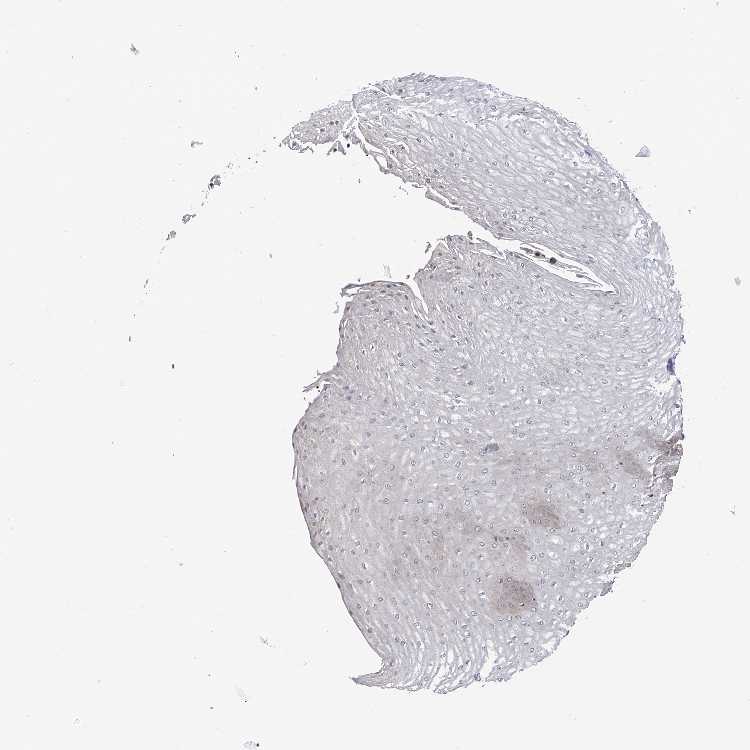

ESOPHAGUS - Antibody stainingi

Antibody staining in the annotated cell types in the current human tissue is reported as not detected, low, medium, or high, based on conventional immunohistochemistry profiling in selected tissues. This score is based on the combination of the staining intensity and fraction of stained cells.

Each image is clickable and will lead to virtual microscopy that enables deeper exploration of all samples and also displays staining intensity scores, fraction scores and subcellular localization as well as patient and tissue information for each sample.

Antibody HPA035123

Squamous epithelial cells Medium